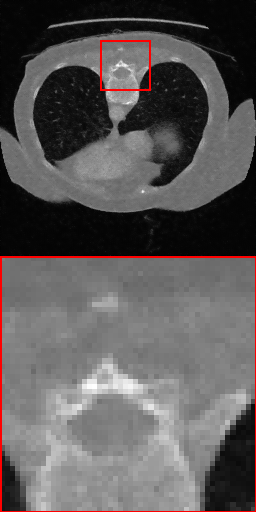

3.4 Results

Our quantitative analysis of results for removing synthetic and real microscopy noise is shown in Tables 2 and 3. Table 2 lists the average inference times for 512×512512\times 512 pixel images from the FMD dataset. Our proposed approach N2D achieves the best performance for synthetic noise removal and second best performance for real microscopy noise, outperformed only by N2S. However, the inference time of our method is significantly lower than N2S. This combination of strong performance and low computational cost emphasizes the strength of our method, positioning it as a competitive alternative to larger and expensive methods. Figures 3 and 4 visualize the denoising results, demonstrating that our method uniquely delivers high-quality results without hallucinating background artifacts, and maintaining high levels of detail fidelity.

Refer to caption

(a) Input

(b) N2V

(c) N2S

(d) ZS-N2N

(e) Ours

(f) GT

Figure 3: Our method is the only one that maintains the fidelity of the foreground while keeping the background smooth without artifacts.